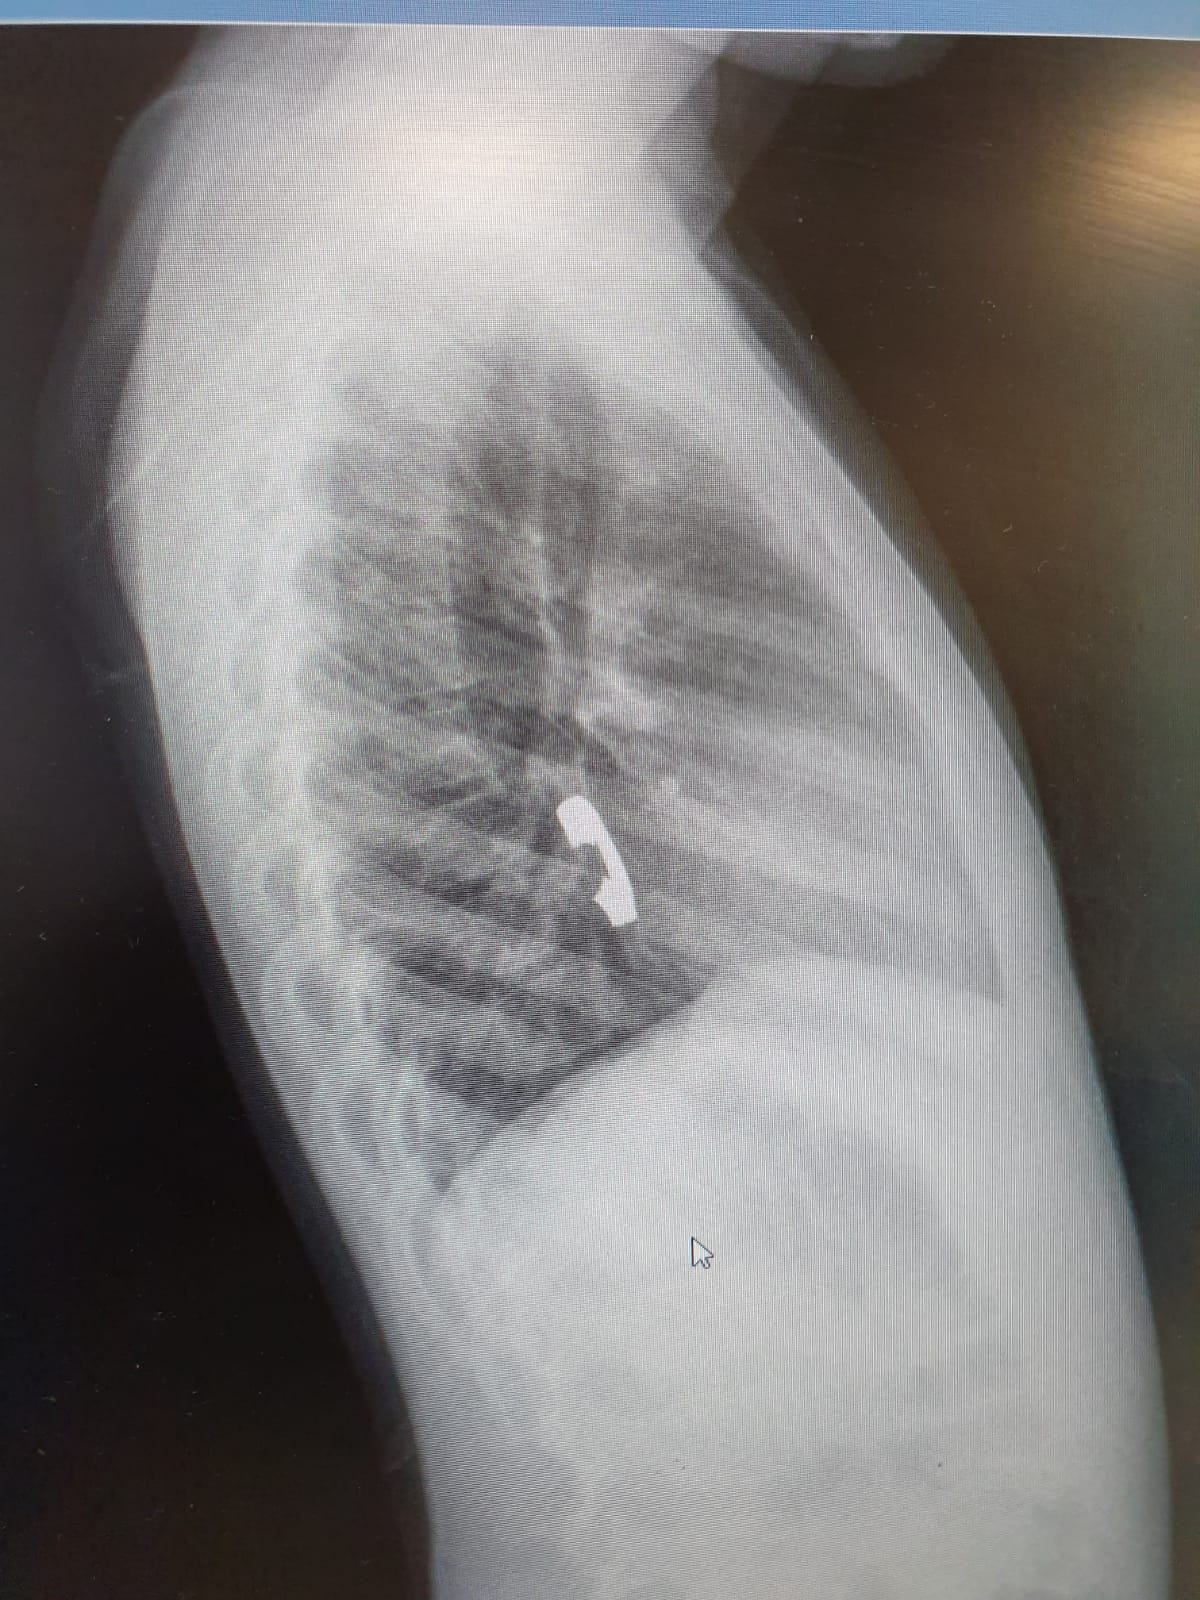

שירה, כך על פי הדיווח שקיבלו הצוותים הרפואיים ב'זיו', בלעה את הטבעת שמצאה בגן הילדים בו היא לומדת. לאחר שהיא חשה כאבים באיזור החזה, היא הובהלה לבית החולים, שם בוצעו צילומים ולאחר שהראו כי הטבעת נתקעה בושט, הוחלט לבצע פעולת גסטרוסקופיה בהרדמה מלאה להוצאתה.

בשל היותה של הטבעת חתוכה, נדרשה תשומת לב גדולה יותר ורמת דיוק גבוהה, על מנת לא לפצוע את הנתיב החוצה.